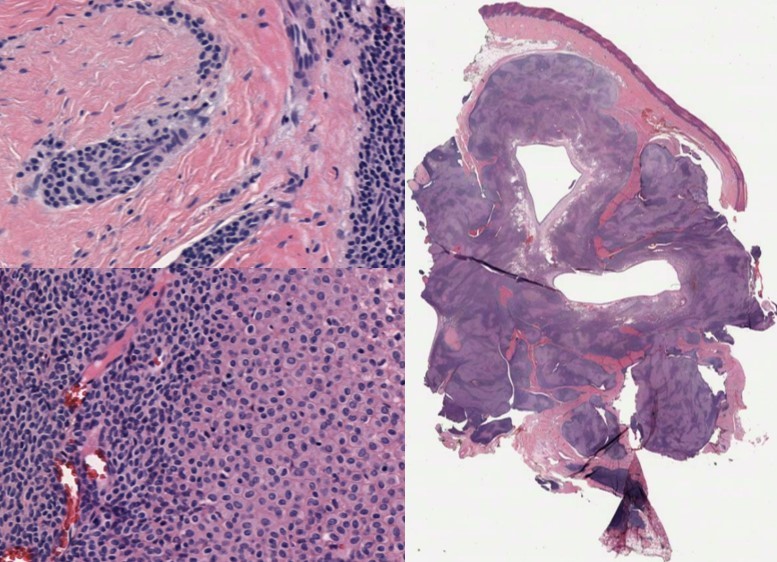

30 yo male with ankle mass.

Chondroid Syringoma